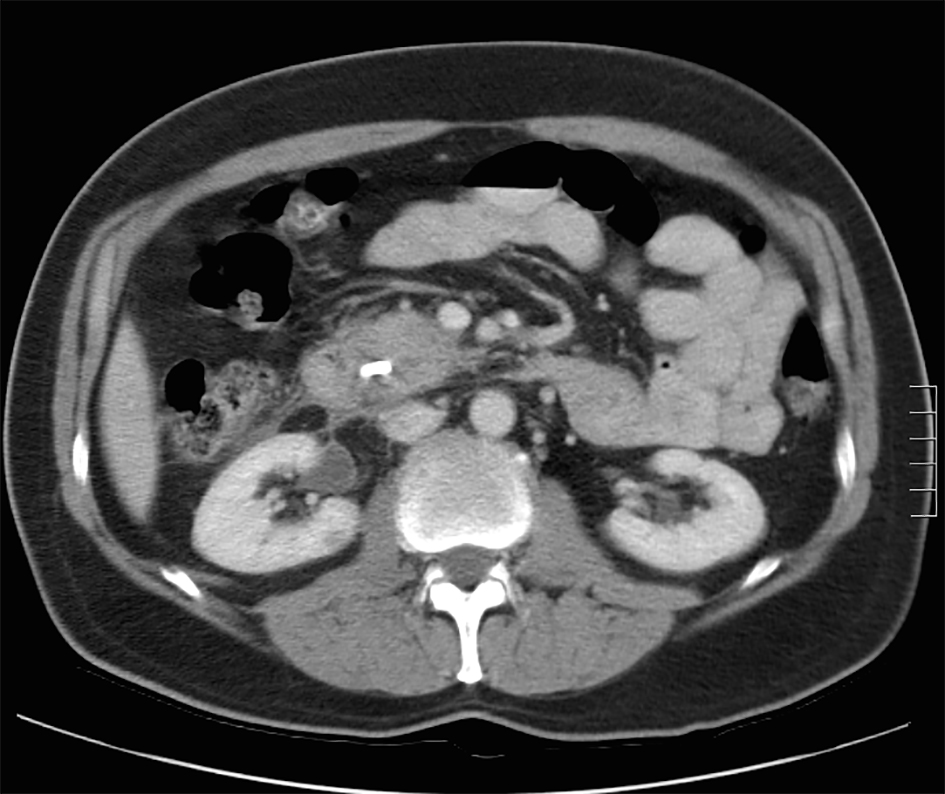

Pancreatic cystic lesions are infrequent but can pose a diagnostic challenge. They can represent simple cysts, pseudocysts due to previous acute or chronic pancreatitis or cystic pancreatic tumors.